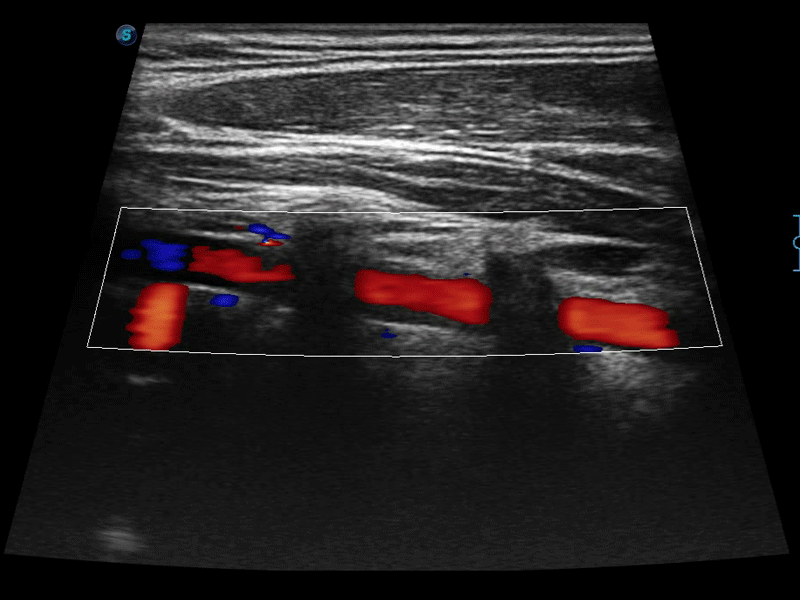

凸阵、线阵和相控阵探头进行实时扫描时,开启扩展成像模式,可以扩展超声图像视野,以便更完整地查看大的病灶或组织器官的解剖结构。

通过色彩血流和实时宽景相结合,可观察到完整的静脉或动脉的血流,方便医生检查。实时扫查过程中,如有任何操作失误也可以很容易地进行回扫擦除,而不会中断扫查。